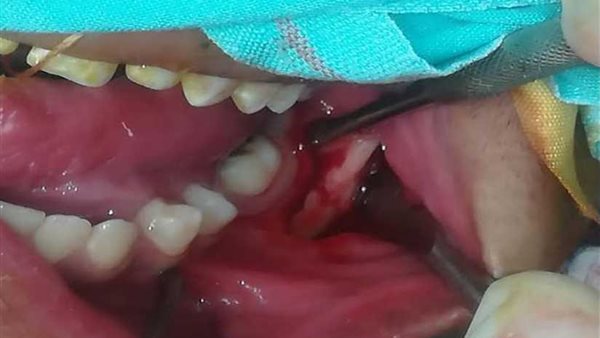

وأوضح الدكتور سمير حلاوة استشاري جراحة الوجه والفم والفكين والذي اجري العملية، بأنه بعد نقل المريض إلى مستشفى «التأمين الصحي النموذجي ببنها» قادمًا من أحد المستشفيات في حالة حرجة، تم على الفور إجراء الكشف الإكلينيكي والإشعاعي للمريض الذي تبيّن انه يعاني من كسر بزاوية الفك السفلى بالجهة اليسرى أدى إلى انفصال الفك السفلي عن الفك العلوي.

وأضاف أن العملية الجراحية استغرقت حوالي ساعتين في غرفة العمليات، حيث تُعدُّ من العمليات المعقدة وذلك بسبب الكسور الموجودة في الفك، وكانت العملية عبارة عن رد مفتوح مع تثبيت الفك السفلي بشرائح ومسامير معدنية، وتم بعد ذلك غلق الفم وتثبيت الفكين معًا بواسطة أسلاك مثبتة بالأسنان العلوية والسفلية، وسوف يتم إزالة هذه الأسلاك لاحقًا وفتح الفم في مدة تتراوح ما بين الثلاثة أو أربعة أسابيع ليستطيع المريض بعدها أن يستأنف نشاطه الطبيعي وحياته العملية.